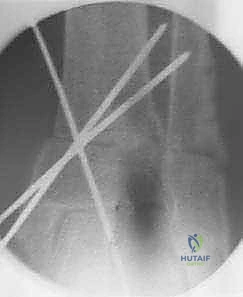

5. التثبيت الصلب وزراعة الطعم العظمي

في حالة "فتح الإسفين"، يتم وضع طعم عظمي (يؤخذ غالباً من عظم الحوض للمريض أو طعم صناعي متقدم) لملء الفراغ. بعد ذلك، يقوم الدكتور هطيف بتثبيت العظم في وضعه الجديد القويم باستخدام شرائح معدنية تشريحية مصممة خصيصاً لهذه المنطقة (Anatomical Locking Plates) ومسامير قوية. هذا التثبيت الصلب يضمن التئام العظم بشكل صحيح.